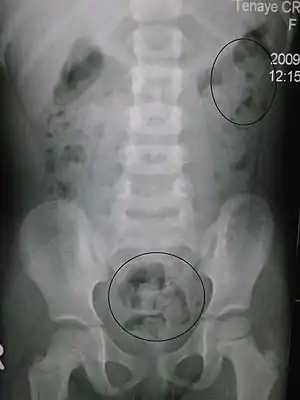

| Constipation in a young child seen on X-ray. Circles represent areas of fecal matter (stool is white surrounded by black bowel gas). | |

Abdominal X-rays are generally only performed if bowel obstruction is suspected, may reveal extensive impacted fecal matter in the colon, and may confirm or rule out other causes of similar symptoms.[25][17]